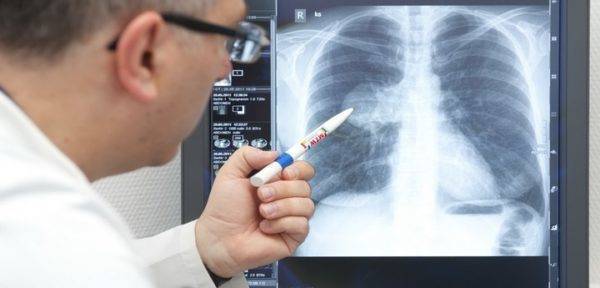

- Сделать рентген (к сожалению, пока не в каждой больнице есть аппаратура для обследования лежачих больных). Скопившаяся в лёгких жидкость на плёнке даст тени и уменьшение прозрачности, но «картинка» будет неотличима от других лёгочных болезней – например, бронхопневмонии.

- рентгенография органов грудной клетки;

В первый же день будут назначены антибиотики с широким спектром действия, рентгенологическое обследование, купирование симптомов дыхательной дисфункции и противокашлевые препараты.

- Рентген. С помощью него можно обнаружить кровяной застой в малом круге и увеличение правых сердечных отделов.